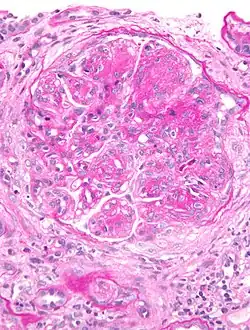

| Micrograph of glomerulus in membranoproliferative glomerulonephritis with increased mesangial matrix and increased mesangial cellularity. Kidney biopsy. PAS stain. | |

The GBM is rebuilt on top of the deposits, causing a "tram tracking" appearance under the microscope.[17] Mesangial cellularity is increased.[18]